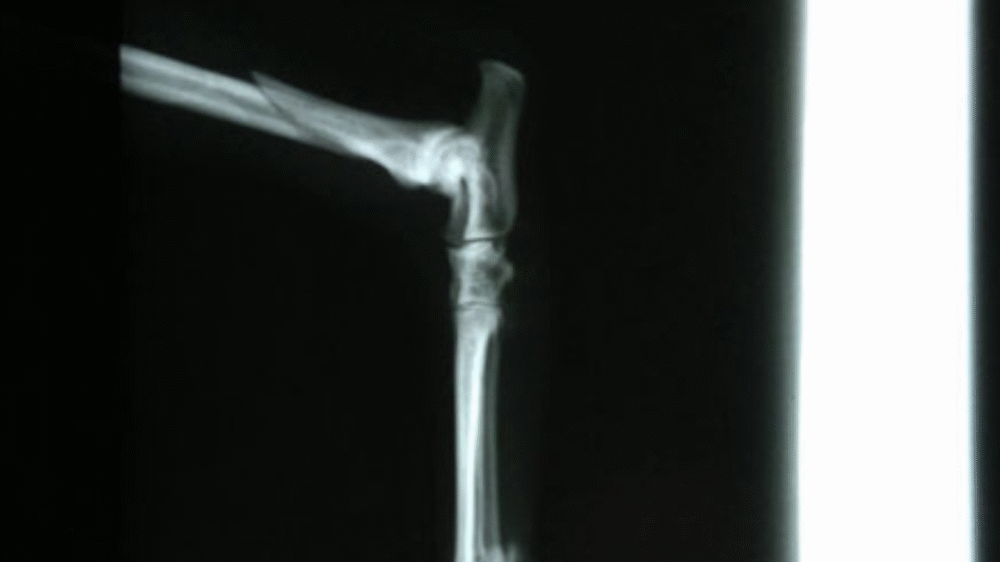

Y Fracture Repair

In a Springer Spaniel.